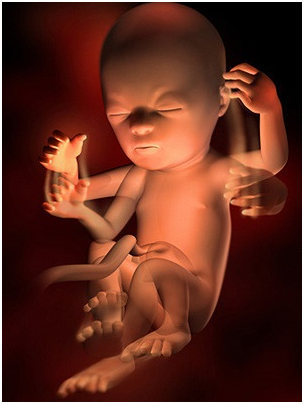

怀孕第28周胎儿图 从现在开始,你就进入了孕晚期,要注意的事情很多呦!你要每天做胎动...

怀孕第28周胎儿图 从现在开始,你就进入了孕晚期,要注意的事情很多呦!你要每天做胎动... -